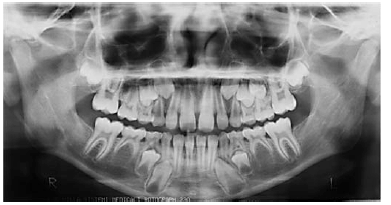

Tendo como base a imagem apresentada, que reproduz uma radiografia panorâmica e os conhecimentos odontológicos correlatos, julgue os itens a seguir.

Tendo como base a imagem apresentada, que reproduz uma radiografia panorâmica e os conhecimentos odontológicos correlatos, julgue os itens a seguir.

Tendo como base a imagem apresentada, que reproduz uma radiografia panorâmica e os conhecimentos odontológicos correlatos, julgue os itens a seguir.

Tendo como base a imagem apresentada, que reproduz uma radiografia panorâmica e os conhecimentos odontológicos correlatos, julgue os itens a seguir.

Tendo como base a imagem apresentada, que reproduz uma radiografia panorâmica e os conhecimentos odontológicos correlatos, julgue os itens a seguir.